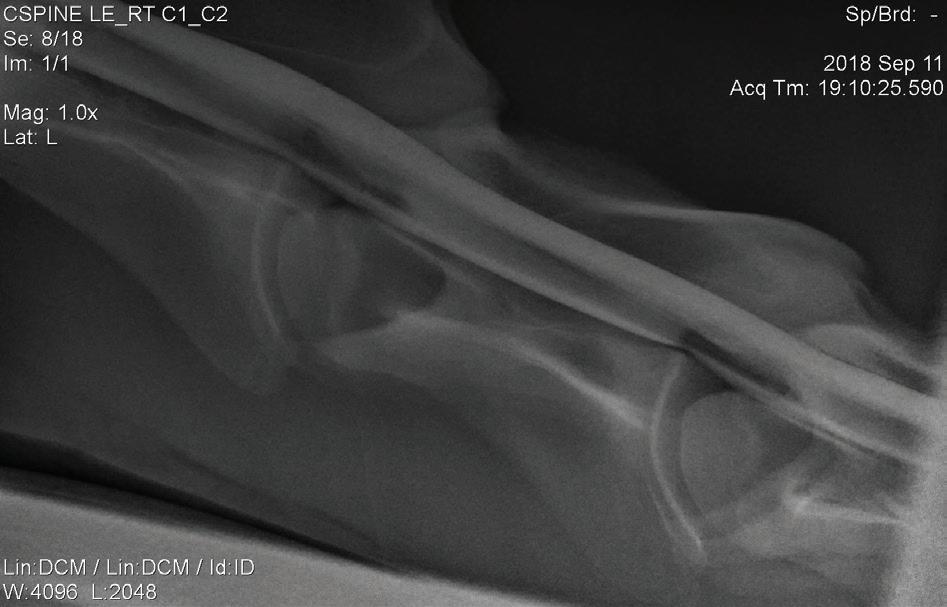

Sex: Gelding

Weight: 563 kg

PRESENTATION

The horse was presented to our hospital on 24 January 2020. The owner reported that the horse was normal before going to the breakers for 5 weeks to begin its education. When arriving home, the horse was immediately noted to have a hind limb problem (when circling), with a swollen left hind leg. Since this time, intermittent abnormalities were suspected by the owner. The owner noted that the horse had lost weight since being at the breakers.

INITIAL DIAGNOSTICS

Neurological examination

A neurological examination can be divided into four sections2:

1. Evaluation of mental status (observing the horse from a distance e.g. in a stable or yard)